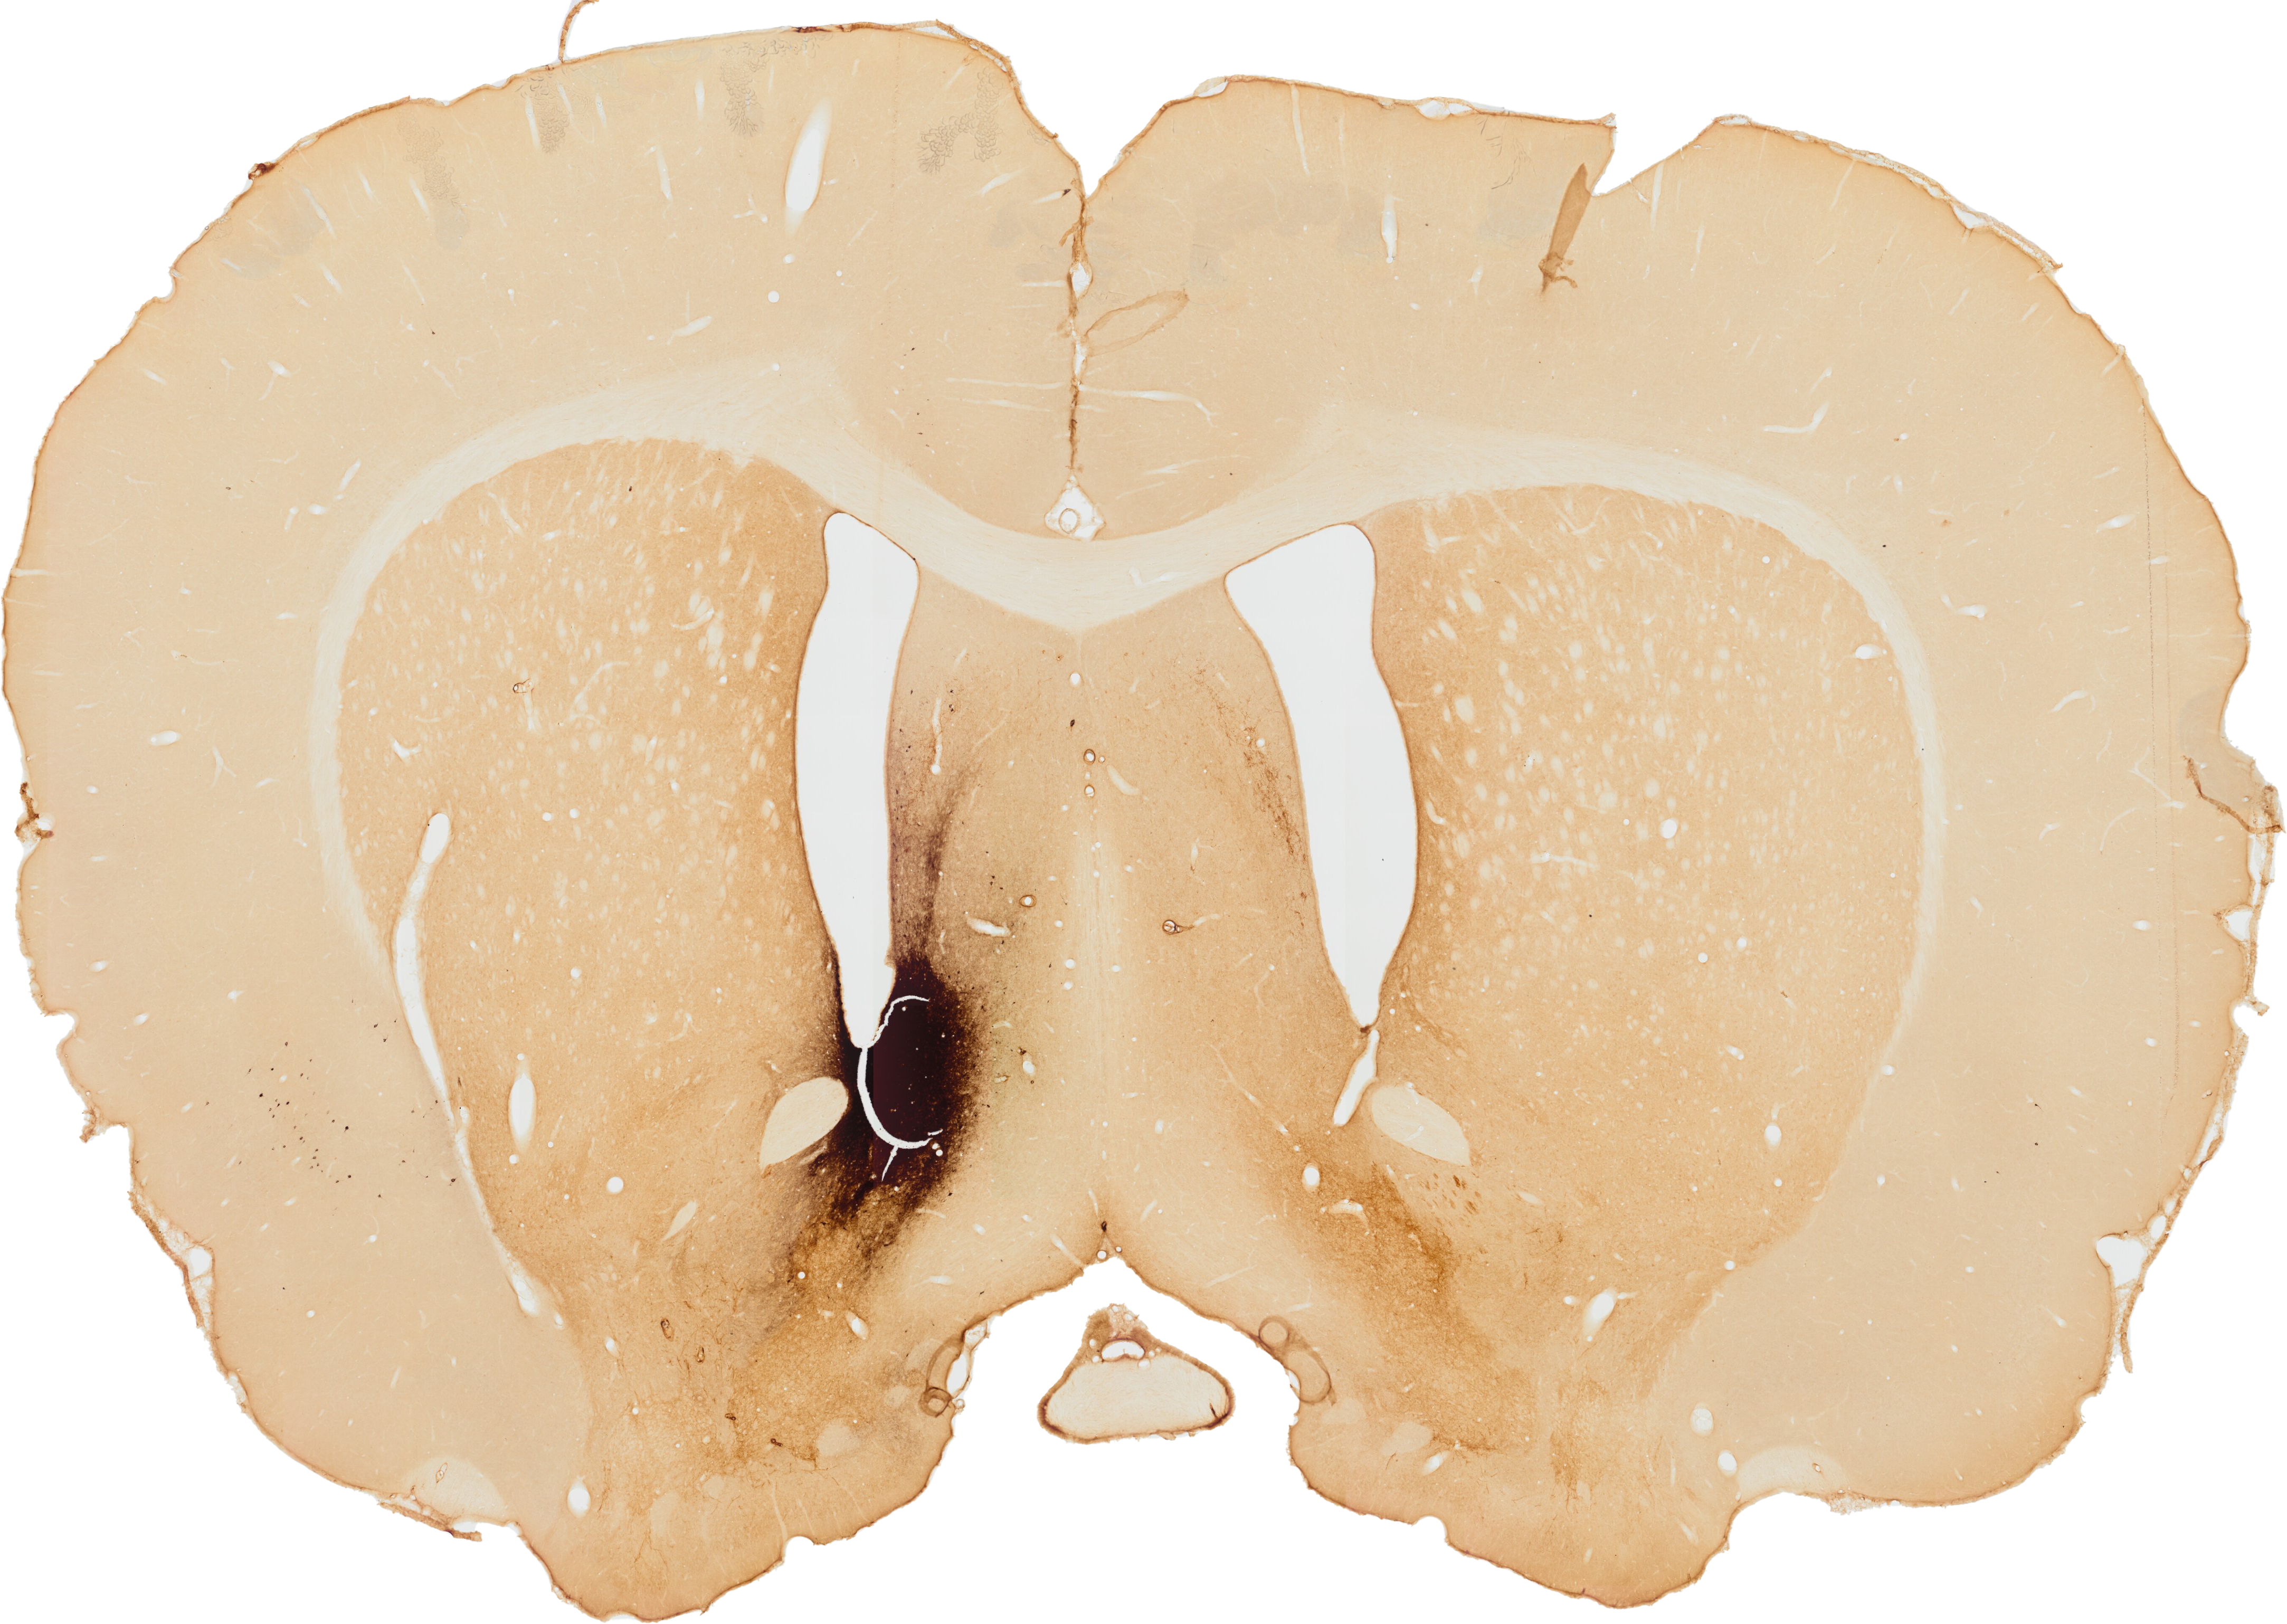

The nucleus accumbens (Acb) is a brain structure that is a central part of the limbic system. It receives input from the hippocampus, amygdala, thalamic nuclei and the medial prefrontal cortex,1 This information is being integrated in the Acb and encodes the prediction of the reward and probability of a behavioral response.2 The output of the Acb is sent to several motor systems, such as the pallidum and the hypothalamic nuclei.3, 4

In 1990 Henk Berendse et al. performed a tracing study to analyze what brain structures project to the Acb.5 This was done by injecting the retrograde tracer CTB (cholera toxine subunit B) into the Acb. This tracer makes it possible to visualize the brain structures that project to the Acb by staining the cell bodies in the brain that project to the injection site. On the figure on the left you can see the injection site into the Acb.

Nucleus Accumbens injection side